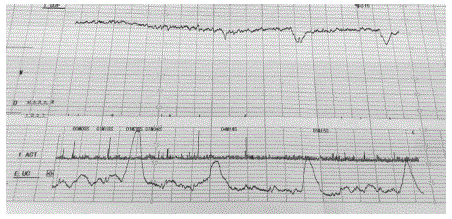

O partograma abaixo caracteriza:

Vitalidade fetal: tônus adequado, movimentação corpórea e respiratória presentes, índice de líquido amniótico de 4,2 cm. Cardiotocografia apresentada.

Qual é a conduta adequada neste momento?